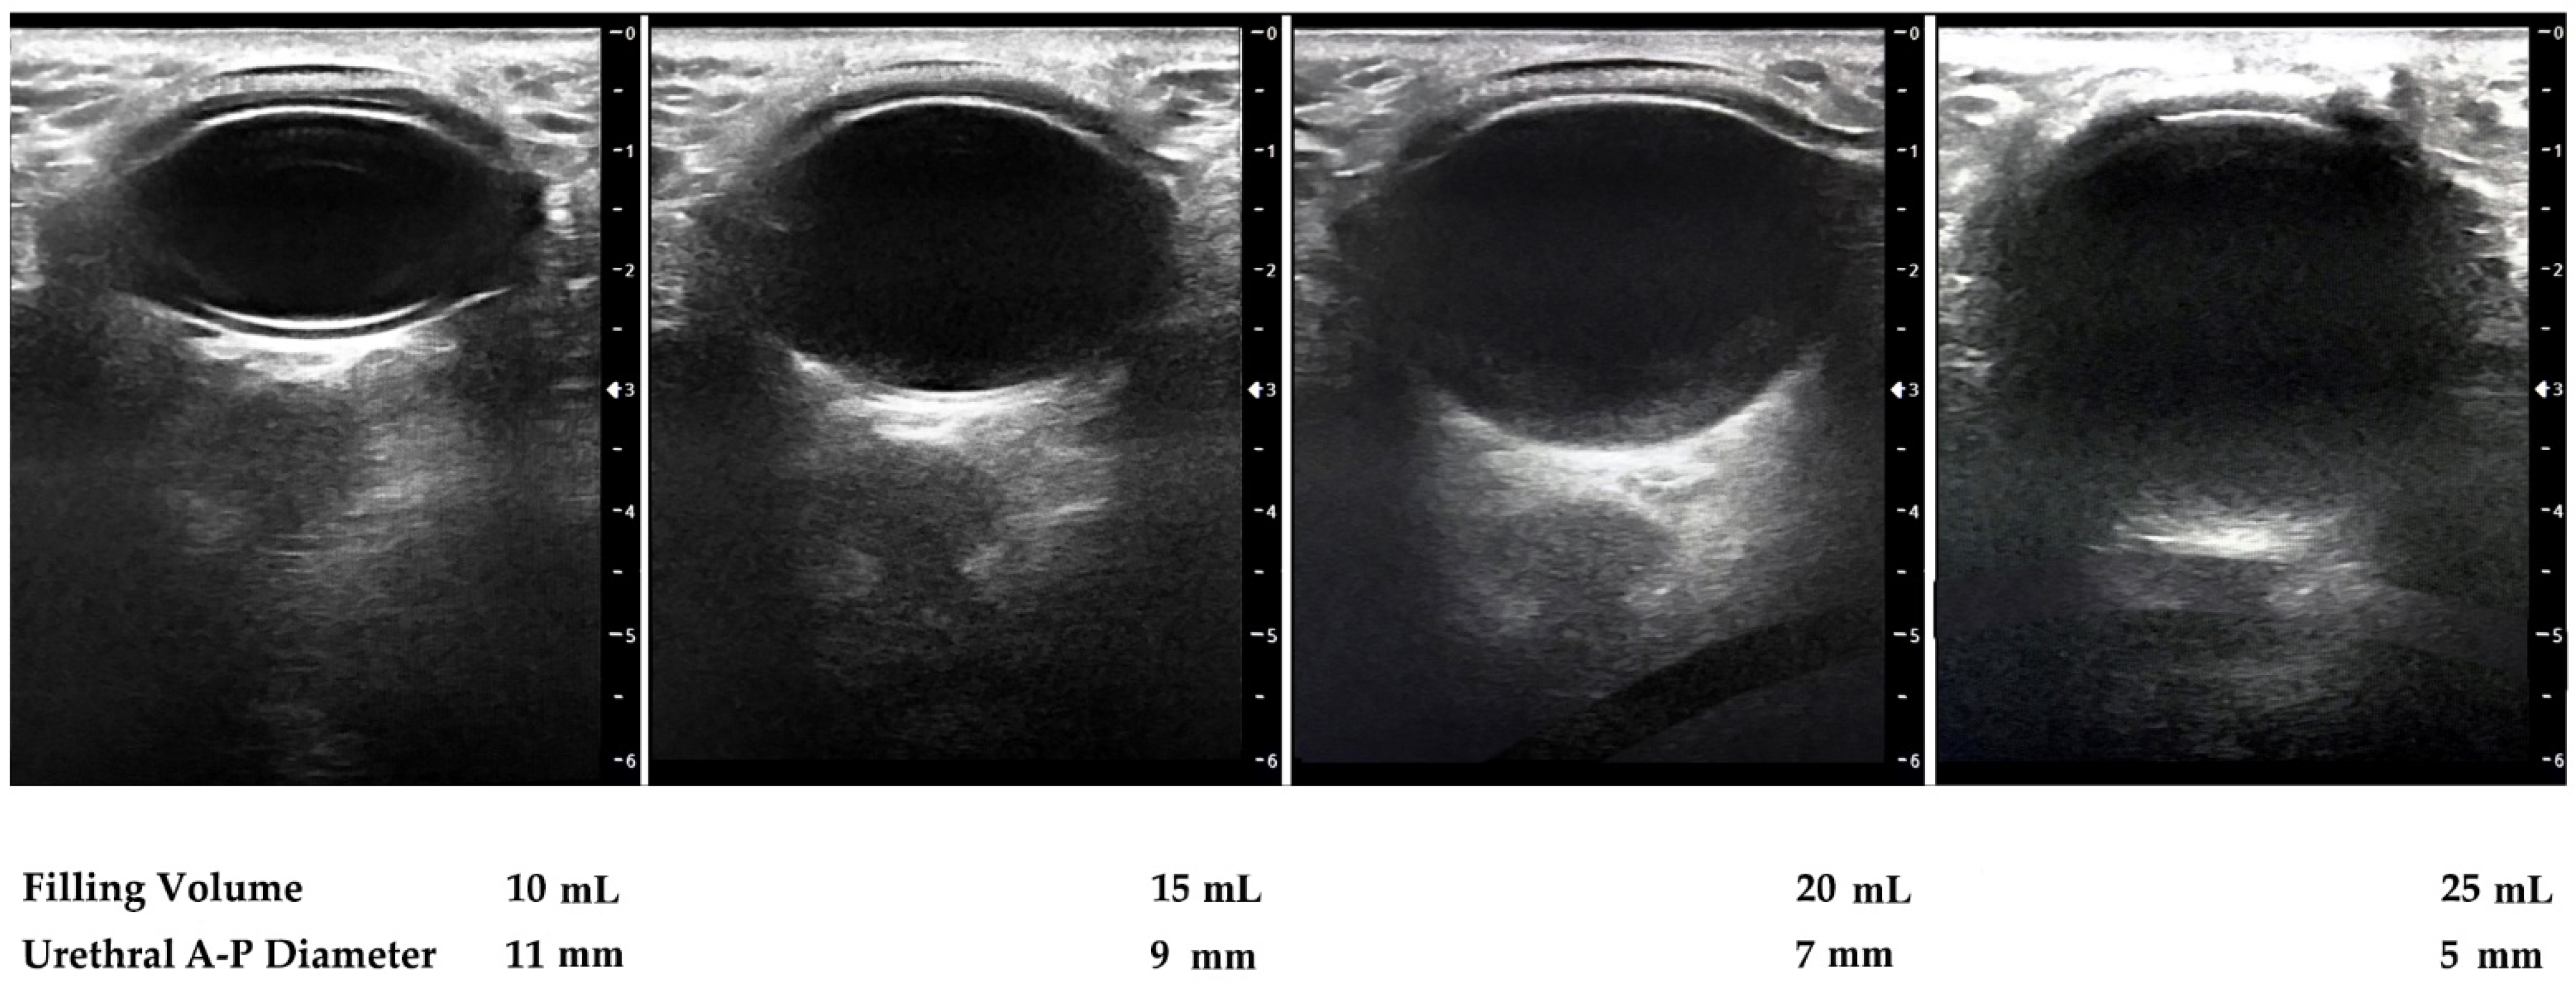

Additionally, ultrasound images performed after ATOMS adjustment at different times for serial postoperative filling in a case needing progressive filling up to 25 mL show that ATOMS filling elongates the transversal urethral diameter whereas it reduces the antero-posterior diameter (Figure 5).

Figure 5. Sonographic perineal evaluation with lineal probe shows urethral diameter (antero-posterior) diminishes with the increase in ATOMS filling volume.